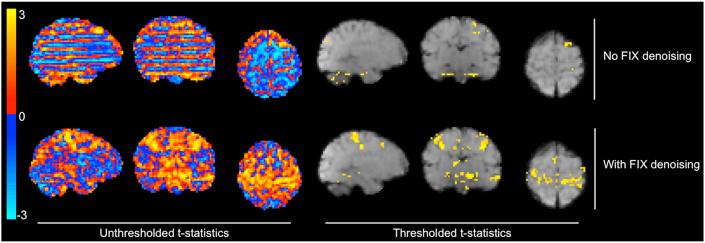

The infant brain is unlike the adult brain, with considerable differences in morphological, neurodynamic, and haemodynamic features. As the majority of current MRI analysis tools were designed for use in adults, a primary objective of the Developing Human Connectome Project (dHCP) is to develop optimised methodological pipelines for the analysis of neonatal structural, resting state, and diffusion MRI data. Here, in an independent neonatal dataset we have extended and optimised the dHCP fMRI preprocessing pipeline for the analysis of stimulus-response fMRI data. We describe and validate this extended dHCP fMRI preprocessing pipeline to analyse changes in brain activity evoked following an acute noxious stimulus applied to the infant's foot. We compare the results obtained from this extended dHCP pipeline to results obtained from a typical FSL FEAT-based analysis pipeline, evaluating the pipelines' outputs using a wide range of tests. We demonstrate that a substantial increase in spatial specificity and sensitivity to signal can be attained with a bespoke neonatal preprocessing pipeline through optimised motion and distortion correction, ICA-based denoising, and haemodynamic modelling. The improved sensitivity and specificity, made possible with this extended dHCP pipeline, will be paramount in making further progress in our understanding of the development of sensory processing in the infant brain.